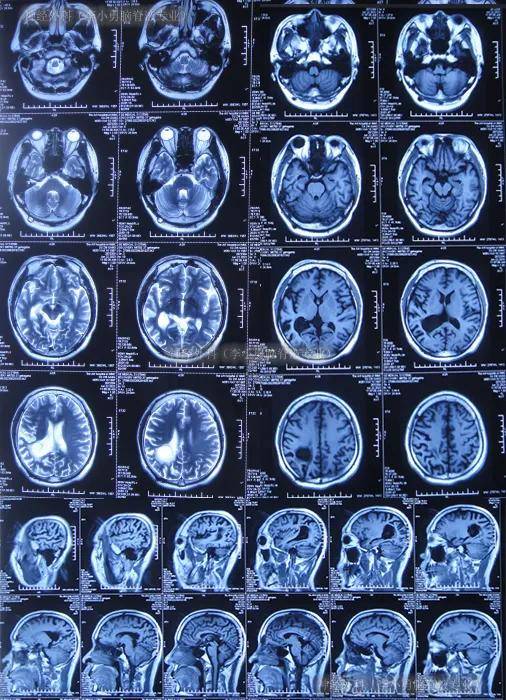

13、脑CT横断面检查通过一系列标准层面图像,帮助医生识别和诊断多种脑部疾病其中,10mm底颅层面能够清晰显示眼眶上部蝶窦中颅凹底以及枕骨和枕大孔等结构在20mm蝶鞍层面,垂体四脑室桥池和桥小脑角池等结构也能够被观察到,这一层特别关注垂体和后颅凹的详细情况30mm的鞍上池层面提供了鞍上池。